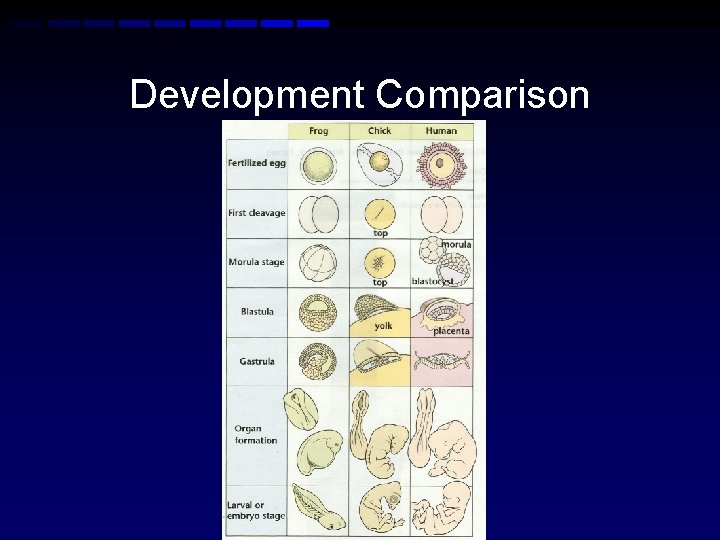

Development Comparison